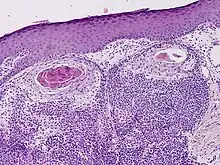

a-c) Malignant hidradenocarcinoma (with ductal differentiation)

Hidradenocarcinoma (also known as malignant hidradenoma, malignant acrospiroma, clear cell eccrine carcinoma, or primary mucoepidermoid cutaneous carcinoma) is a malignant adnexal tumor of the sweat gland. It is the malignant variant of the benign hidradenoma. It may develop de novo or in association with an existent hidradenoma.[1]